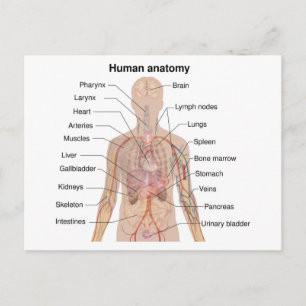

Human Yta Anatomy Relation till organ Poster

Pris258,00 kr

Human Yta Anatomy Relation till organ Poster

Pris258,00 kr

Anatomi i mänskliga organ vykort

Pris23,00 kr

Anatomi i mänskliga organ poster

Pris229,00 kr

Anatomi i mänskliga organ canvastryck

Pris1 425,00 kr

Anatomi i mänskliga organ hälsningskort

Försäljningspris 49,00 kr. Ursprungligt pris 54,00 kr.